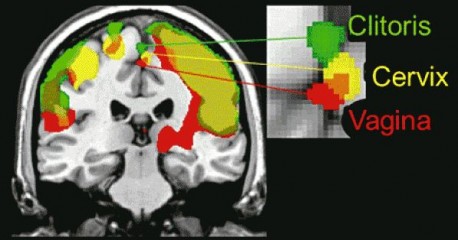

Znanstvenici su koristili magnetsku rezonancu kako bi skenirali mozak te su otkrili da se ova dva načina stimulacije razlikuju po tome što aktiviraju različite dijelove u mozgu.

Međutim, kad su pokušali učiniti isto sa ženskim mozgom, znanstvenici su naišli na neke vrlo zanimljive rezultate. Osim podatka da se vaginalni i klitoralni podražaj značajno razlikuju, znanstvenici su otkrili i da ženske bradavice aktiviraju isti dio mozga kao i genitalna stimulacija.